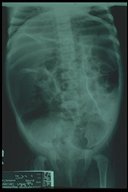

Plain X-ray showed marked dilatation of sigmoid colon and rectum

Plain X-ray showed marked dilatation of sigmoid colon and rectum, the ground glass appearance of retained fecal material in the dilated bowel loop is noted